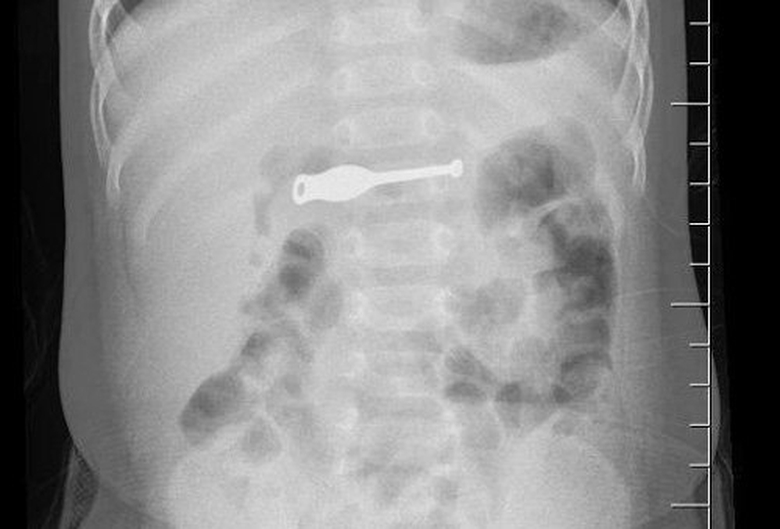

Chiếc que lấy ráy tai nằm trọn trong bụng bệnh nhi |

Các bác sĩ Bệnh viện Sản nhi Quảng Ninh vừa phẫu thuật nội soi gắp dị vật thành công cho bệnh nhi Vũ Phúc Khánh, 10 tháng tuổi (Hải Hà, Quảng Ninh). Bé Khánh nhập viện trong tình trạng đau bụng, quấy khóc. Kết quả chụp X-quang cho thấy dị vật kim loại dài khoảng 10cm ở dạ dày.